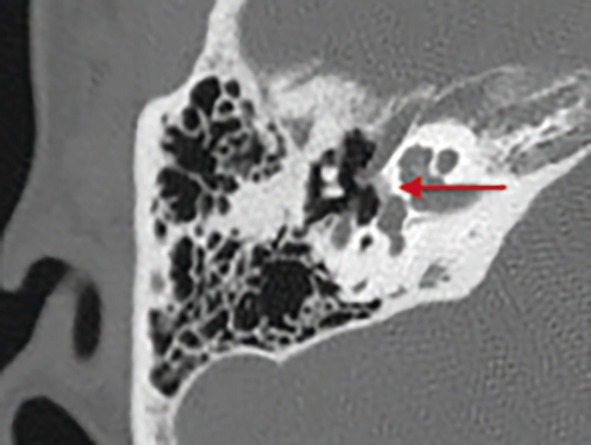

Schwannome du paquet acoustico-facial :

– tumeur rare (1/100 000), bénigne, à croissance lente, se développant le plus souvent aux dépens du nerf vestibulaire inférieur dans le méat auditif interne ;

– suspecté devant une surdité unilatérale ou asymétrique, des troubles vestibulaires (léger déséquilibre, démarche ébrieuse ou embardées ; 50 % des cas) ;

– confirmé par l’IRM qui doit être injectée (le produit de contraste permet de déceler de minuscules schwannomes intracanalaires ou cochléaires ;fig. 3 ).